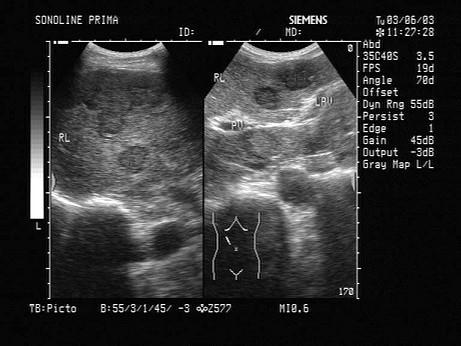

男,62岁,直肠肿瘤术后半年。结合超声声像图,诊断为?(?)A.肝血管瘤B.肝囊肿C.结节性肝硬化D.转移性肝癌E.肝脓肿

问题 男,62岁,直肠肿瘤术后半年。结合超声声像图,诊断为?(?)

选项 A.肝血管瘤 B.肝囊肿 C.结节性肝硬化 D.转移性肝癌 E.肝脓肿

答案 D